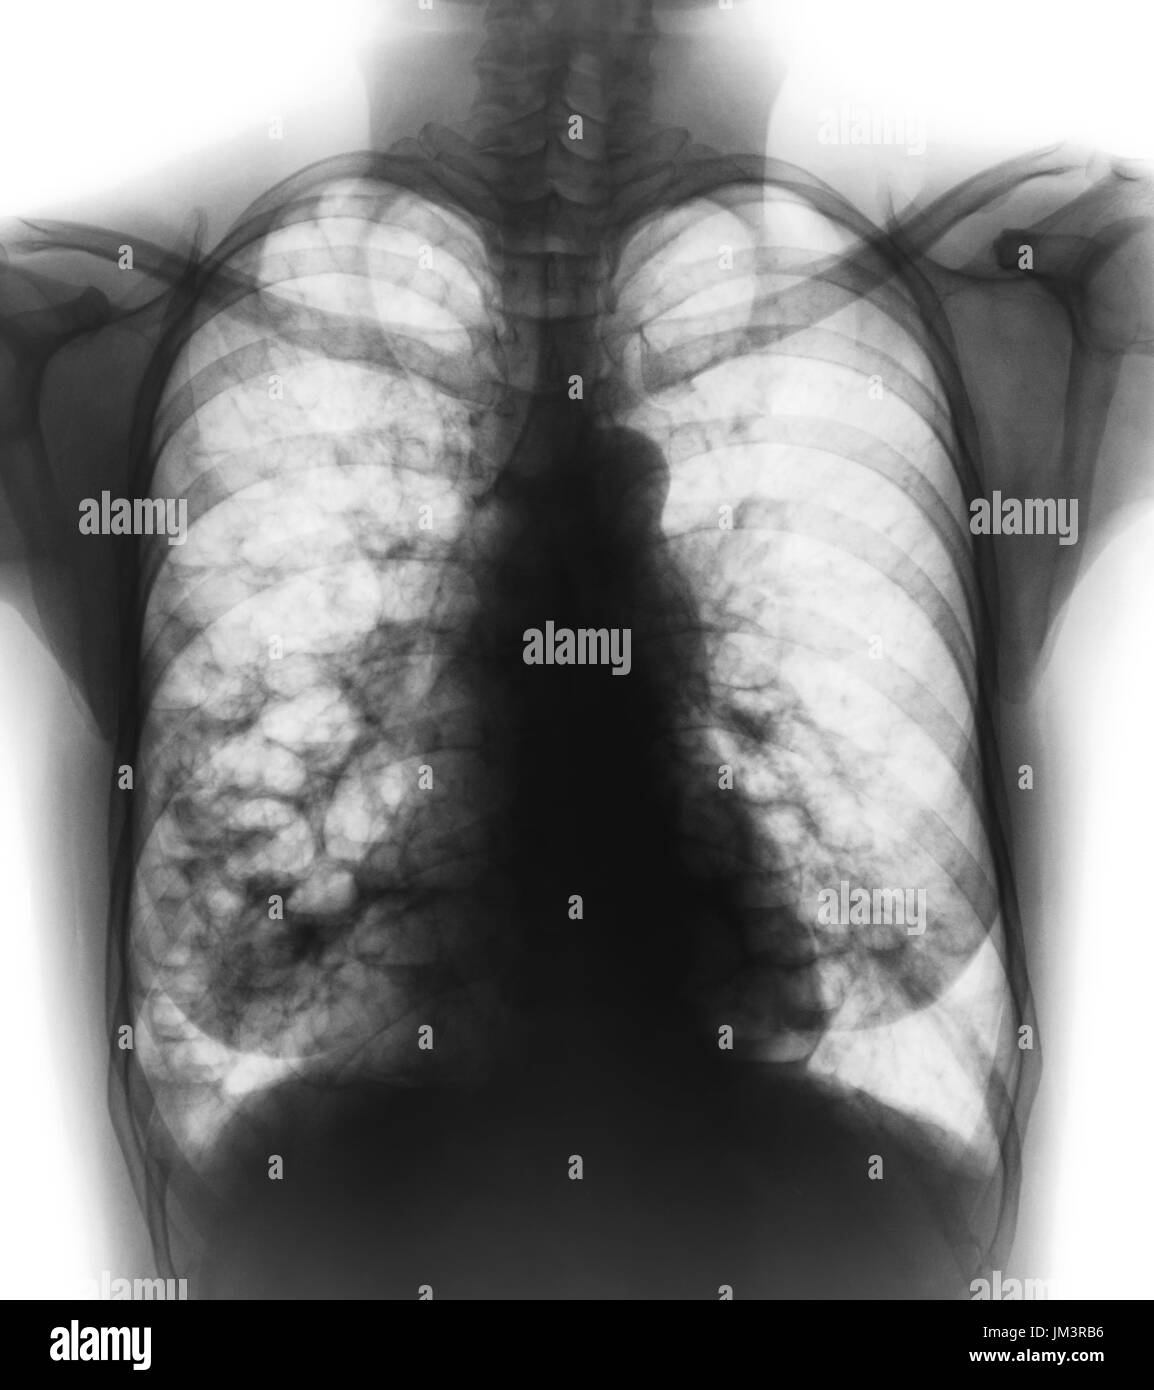

Chest X Ray Of Bronchiectasis . In addition to making the diagnosis, the pattern of. May be normal or may show. Chest radiography is usually the initial study performed in suspected bronchiectasis. Chest ct scan if indicated (e.g., hemoptysis, or concern for pulmonary. Diagnosis of bronchiectasis is usually made using chest computed tomography (ct) scan, the current gold standard method. Shows bronchial dilation, with or without airway thickening. Required to exclude other pathologies. Signs in severe disease include tram lines and ring shadows.

Bronchiectasis . Xray Chest Show Multiple Lung Bleb and Cyst Due To Chest X Ray Of Bronchiectasis Chest ct scan if indicated (e.g., hemoptysis, or concern for pulmonary. May be normal or may show. Diagnosis of bronchiectasis is usually made using chest computed tomography (ct) scan, the current gold standard method. Required to exclude other pathologies. Signs in severe disease include tram lines and ring shadows. Shows bronchial dilation, with or without airway thickening. In addition to. Chest X Ray Of Bronchiectasis.

STOCK IMAGE, xray of the chest frontal view showing bronchiectasis Chest X Ray Of Bronchiectasis In addition to making the diagnosis, the pattern of. May be normal or may show. Chest ct scan if indicated (e.g., hemoptysis, or concern for pulmonary. Signs in severe disease include tram lines and ring shadows. Shows bronchial dilation, with or without airway thickening. Chest radiography is usually the initial study performed in suspected bronchiectasis. Diagnosis of bronchiectasis is usually. Chest X Ray Of Bronchiectasis.